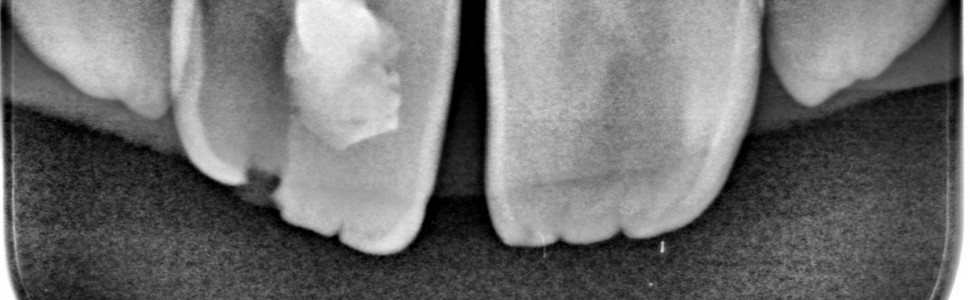

Obecnie stosowanymi metodami leczenia endodontycznego zębów stałych niedojrzałych z martwą miazgą są metody apeksyfikacji z użyciem wodorotlenku wapnia [Ca(OH)2] oraz zamknięcie wierzchołka korzenia materiałem typu MTA. Metody te mają jednak swoje ograniczenia.

Leczenie regeneracyjne powinno się rozważyć jako postępowanie alternatywne. Terapia ta pozwala na odtworzenie w kanale tkanki miazgopodobnej, która umożliwia wzrost korzenia nie tylko na długość, lecz także zwiększenie grubości ścian kanału korzeniowego. Istotną rolę w powodzeniu leczenia regeneracyjnego odgrywa dezynfekcja systemu korzeniowego, a więc wolne od drobnoustrojów środowisko w kanale i tkankach okołowierzchołkowych, sprzyjające gojeniu.

Nowadays, the available methods of endodontic treatment of immature permanent teeth with necrotic pulp are apexification with use of calcium hydroxide and the placement of MTA close to the apical foramen. These methods have its disadvantages.

Regenerative treatment should be considered as an alternative. This therapy allows reconstruction of pulp-like tissue which might induce root formation not only in length but also in thickness. Disinfection of the root canal system, i.e. a germ-free environment in the canal and periapical tissues, plays an important role in the success of the regenerative treatment.